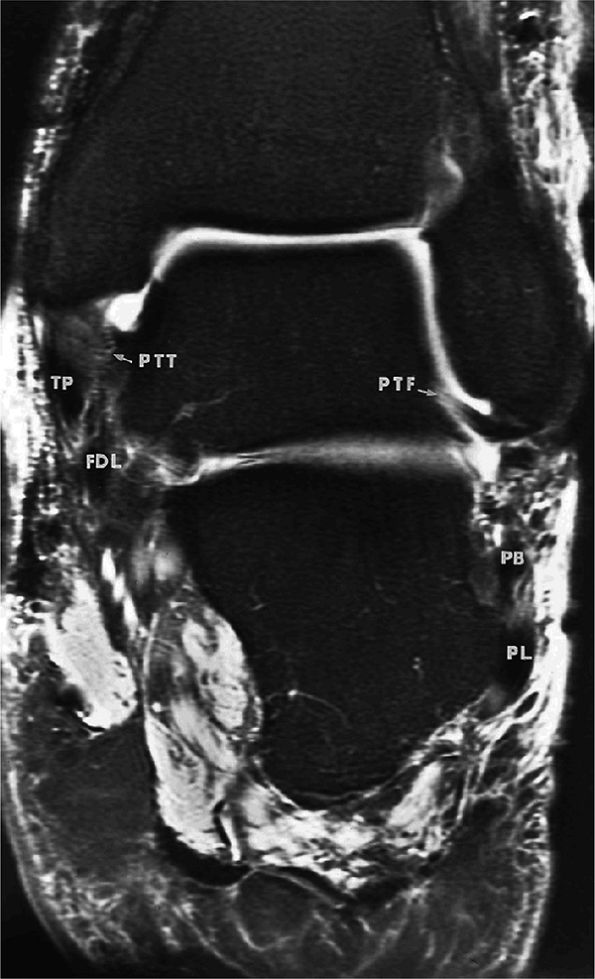

![]() |

FIGURE 5.67 ● Posterior coronal FS PD FSE image at the level of the posterior talofibular ligament (PTF) and posterior tibiotalar ligament (PTT). TP, tibialis posterior; FDL, flexor digitorum longus; PB, peroneus brevis tendon; PL, peroneus longus tendon.